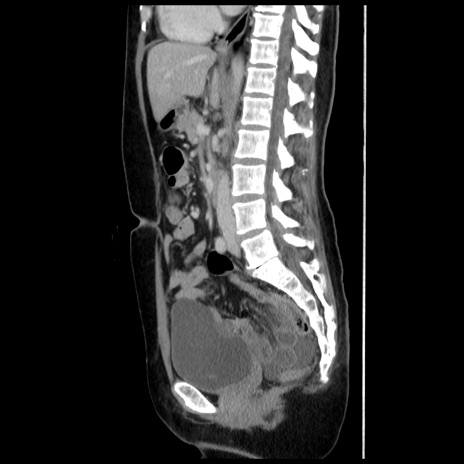

症例10(矢状断像)

【症例】 50歳代女性

【主訴】 腹痛

【現病歴】前日生レバーを食べた。今朝に排便あり。 昼前に突然発症の腹痛を生じ、当院救急外来を受診した。

【既往歴】 子宮筋腫にてで子宮全摘後

【身体所見】 意識清明、腹部:平坦、軟、下腹部やや左を中心に圧痛・反跳痛あり、筋性防御あり

【データ】WBC 7800、CRP 0.07